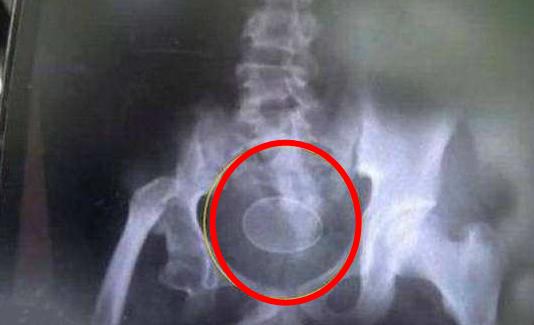

Akmal声称自己肚子里有异物,且从上周开始拉出7颗长的像鸡蛋的东西,父母将他带到当地的萨雅客医院检查。经过X光照射后,确实看到男童的骨盆腔及腹部内有外型极像鸡蛋的物体,检查完毕后没多久,Akmal又在急诊室拉出7颗。